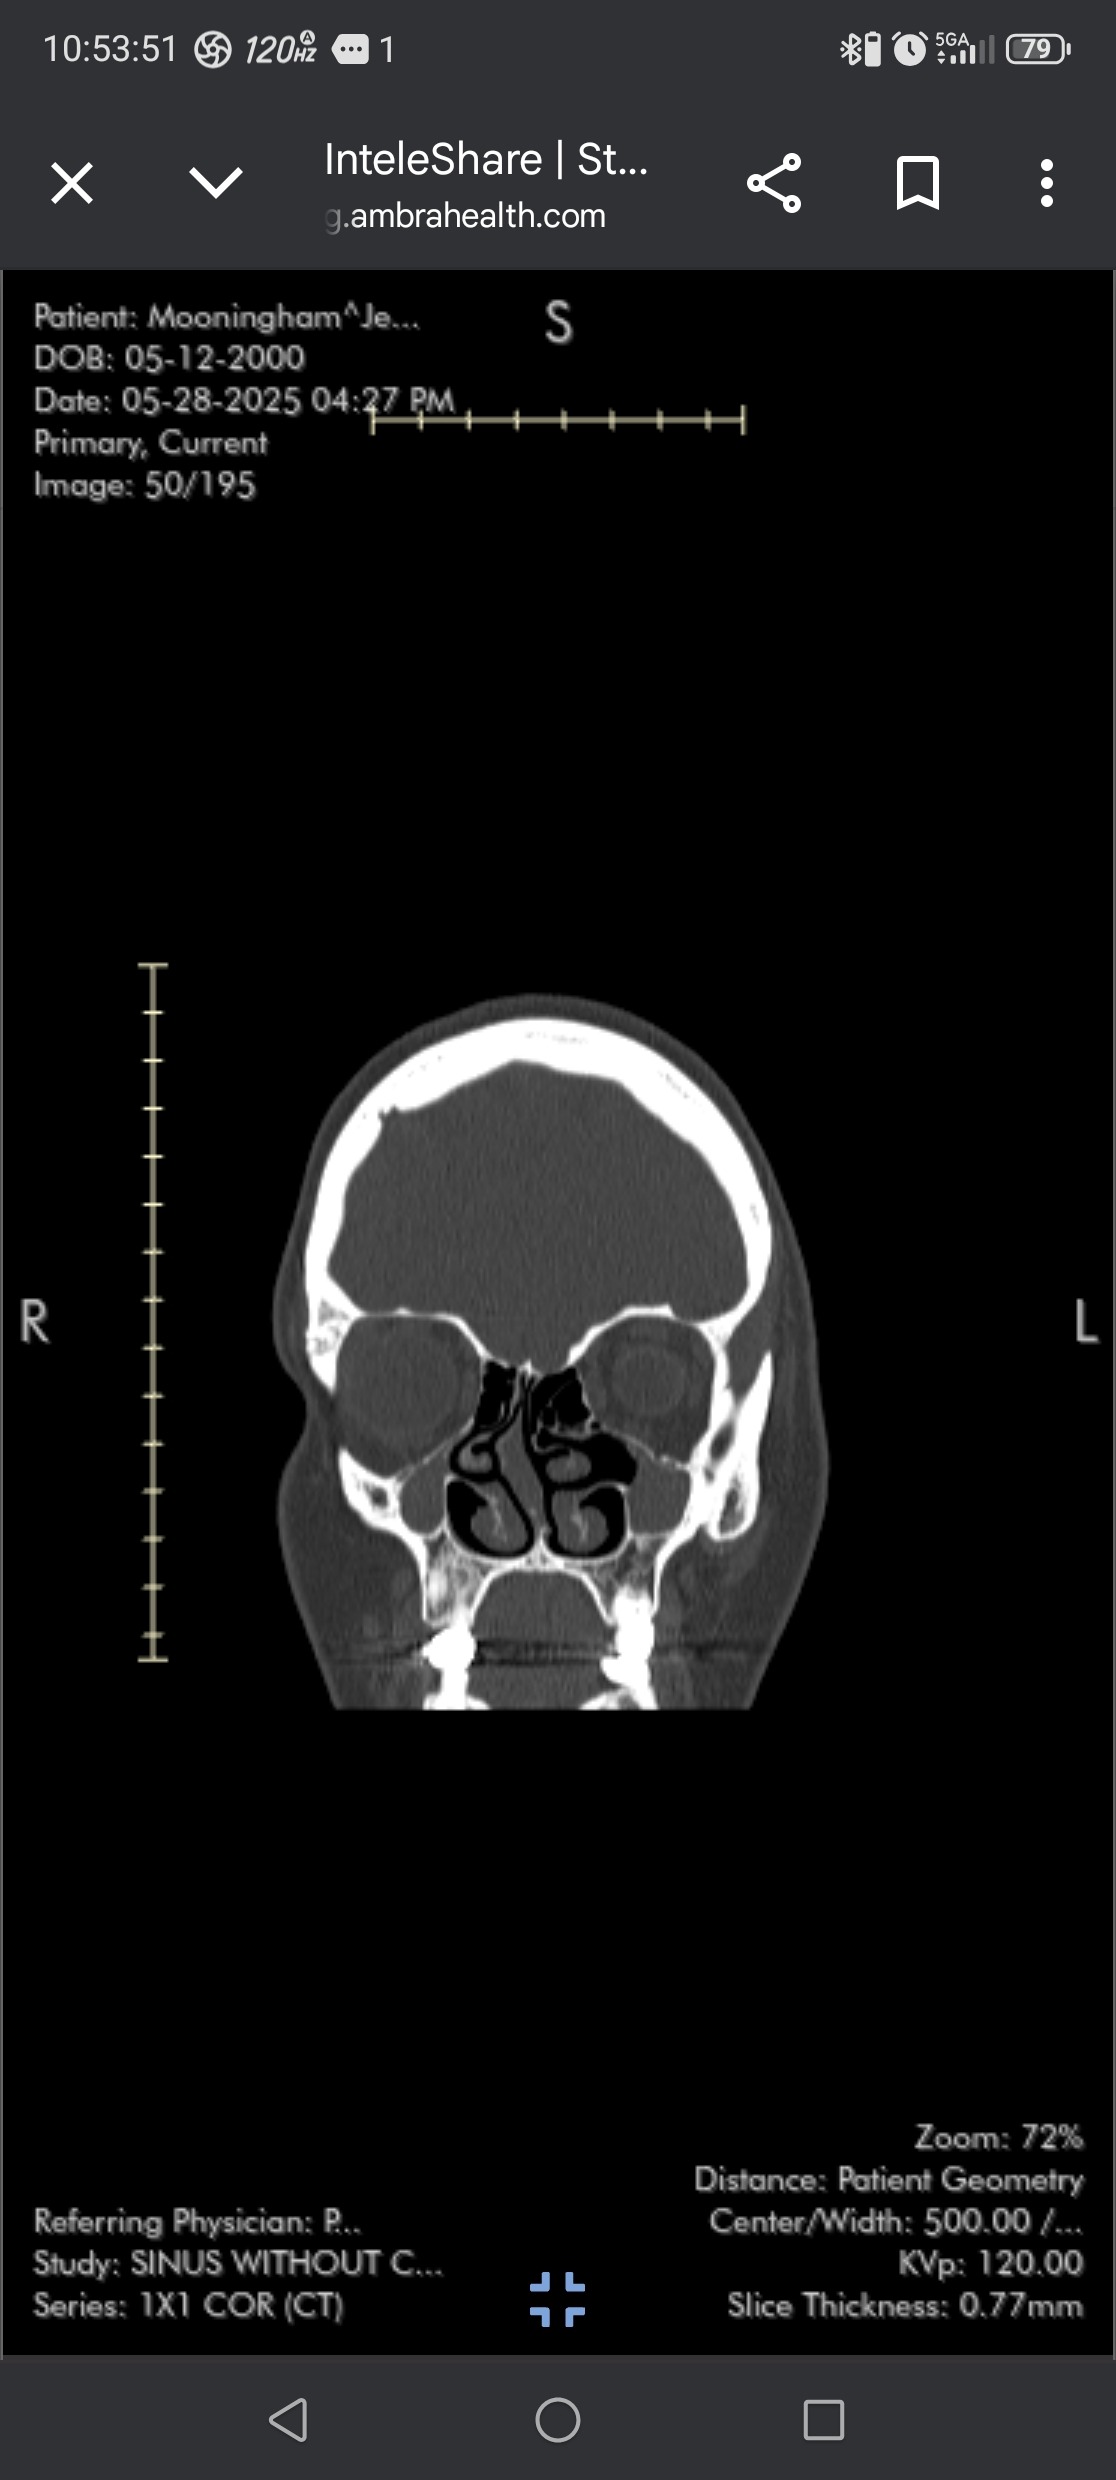

Now at 25, I’m facing the long-term effects: a broken nose, a completely deviated septum, and collapsed sinuses that make it hard to breathe, sleep, or live comfortably day to day.

Correcting the severe septal deviation

Repairing my collapsed sinuses